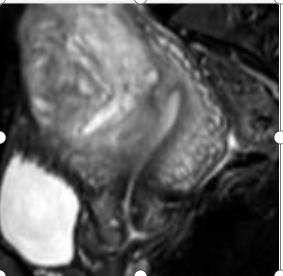

張惠嬌主任詳細(xì)了解了陳女士的病史、病理檢查及免疫組化結(jié)果,認(rèn)真進(jìn)行婦科檢查、結(jié)合磁共振、腫瘤標(biāo)志物檢查,綜合評(píng)估后決定為陳女士實(shí)施腹腔鏡廣泛宮頸切除術(shù)(免舉宮)+前哨淋巴結(jié)切除+子宮肌瘤剔除術(shù)。

術(shù)后病理結(jié)果支持宮頸鱗癌Ib1期、子宮平滑肌瘤診斷。術(shù)后至今半年,陳女士月經(jīng)規(guī)律,經(jīng)量如常,無經(jīng)期腹痛、接觸性出血等不適,經(jīng)宮頸篩查、盆腔磁共振及腫瘤標(biāo)志物檢查等全面評(píng)估,陳女士術(shù)后康復(fù)良好,提示本次保留子宮的廣泛宮頸切除術(shù)是成功的!這是漳州地區(qū)首例保留生育功能的宮頸癌手術(shù),標(biāo)志著正興醫(yī)院婦瘤中心在宮頸癌治療再上新臺(tái)階!